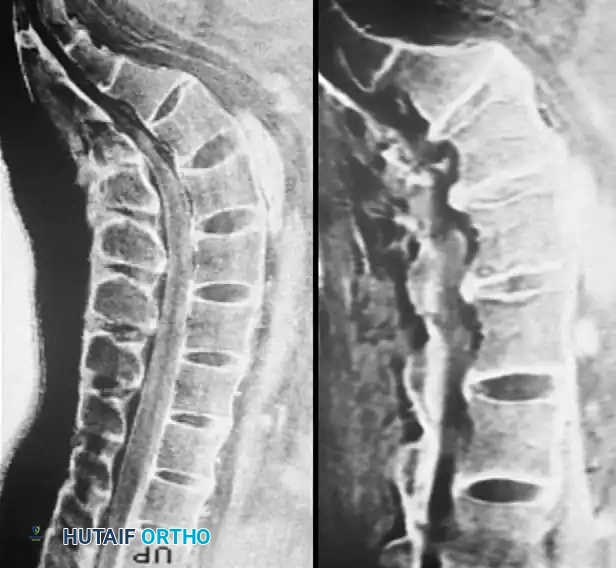

Fig. 39-6 A: MRI Sagittal view of a 45-year-old patient with right C7 radiculopathy. The MRI was inconclusive for a definitive disc herniation.

Fig. 39-6 B: MRI Axial view of the same patient, failing to clearly delineate the intraforaminal pathology.